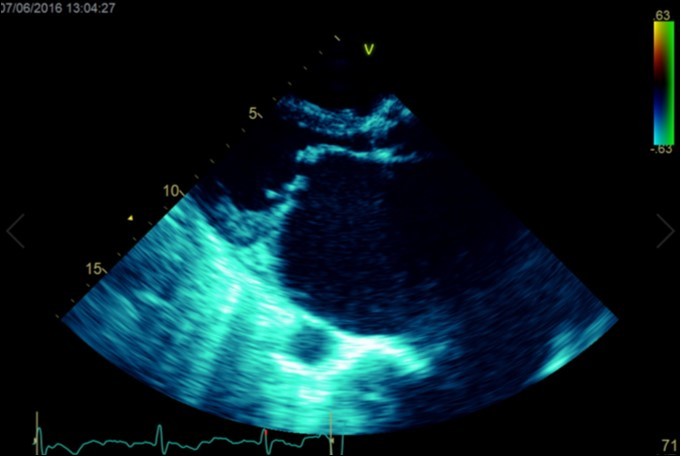

A dramatically dilated left atrium was seen on a TTE (see Figure 2a, Figure 2b, Figure 2c, and Figure 2d). Severe mitral stenosis with associated regurgitation was evident, with a mean gradient across the valve of 11mmHg and a hyperdynamic left ventricle. The left atrial volume measured by Simpson’s biplane method (see Figure 2c) was 2108mL, or 1548.5 ml/m2, based on height 1.55 metres and weight 44 Kg. Normal left atrial volume in a woman is 16 - 34 ml/m21. The computed tomography scan (CT) chest AP view (see Figure 3) is also shown.

Figure 2b.Transthoracic echocardiogram Parasternal long axis view. Findings include severe mitral stenosis (‘hockey-stick’ appearance to mitral valves), raised left atrial pressure (interatrial septum fixed and bowed to right)

Transthoracic echocardiogram Parasternal long axis view. Findings include severe mitral stenosis (‘hockey-stick’ appearance to mitral valves), raised left atrial pressure (interatrial septum fixed and bowed to right)